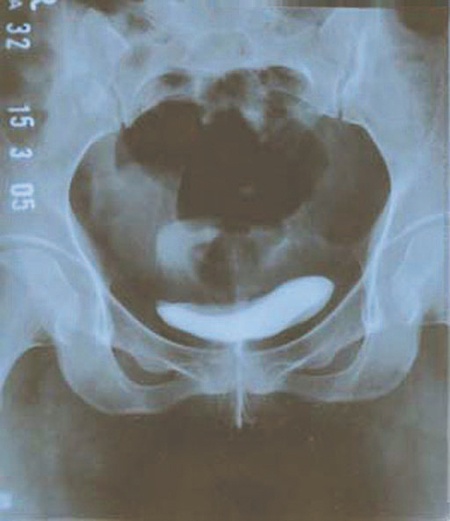

تشخيص دقيق للجهاز البولي باستخدام الأشعة

عندما لا يشفى المريض من مرضه مع المداومة على استخدام العلاج الموصوف له من قبل الطبيب عندها يقوم الطبيب بطلب تصوير خاص للكلى والجهاز البولي عامة بواسطة الأشعة الصوتية أو الملونة ويسمى هذا النوع من التصوير intravenous pyelogram IPV، وتتم العملية بواسطة حقن صبغة معينة في الوريد يمكن مشاهدتها بواسطة التصوير بالأشعة السينية ومن ثم يتم أخذ صور متلاحقة للجهاز البولي على فترات زمنية معينة يشاهد من خلالها حدود الجهاز البولي ليُمكن الطبيب من مشاهدة أي تغيرات حتى لو كانت صغيره في المجرى البولي قد تساعده في فهم الحالة.